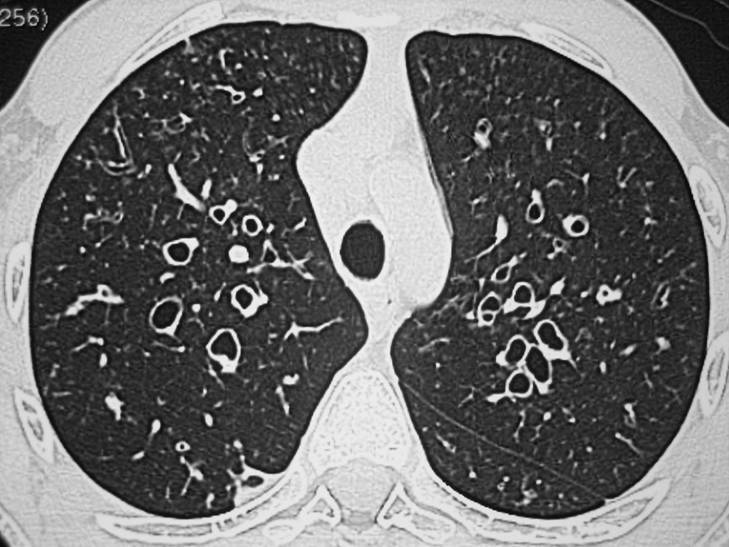

1. Cilindricas

1. El primer cambio histológico es la pérdida del epitelio ciliado, reemplazado por epitelio cuboideo y escamoso. Es la forma más frecuente

2. Varicosas

1. Con la evolución se afectan las fibras elásticas y aparecen cicatrices con fibrosis intersticial que dilata la vía aérea por tracción, presentan bordes irregulares alternando áreas dilatadas con áreas de constricción

2. Saculares

1. Se afectan las capas musculares y el cartílago, con forma quística, un diámetro progresivamente mayor y el contorno abombado, finaliza en un fondo de saco ciego y es la forma más grave

1. Radiografía de tórax